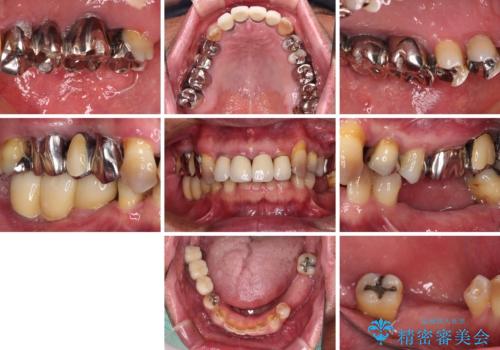

- 奥歯が咬みにくく、前歯がぐらぐらするとのことで来院された患者様です。

咬合力が強く、奥歯が欠損している状態でした。

欠損部はインプラントによる補綴治療を行うこととし、臼歯部が安定した後に、上下前歯部をオールセラミッククラウンにて補綴治療を行うこととしました。